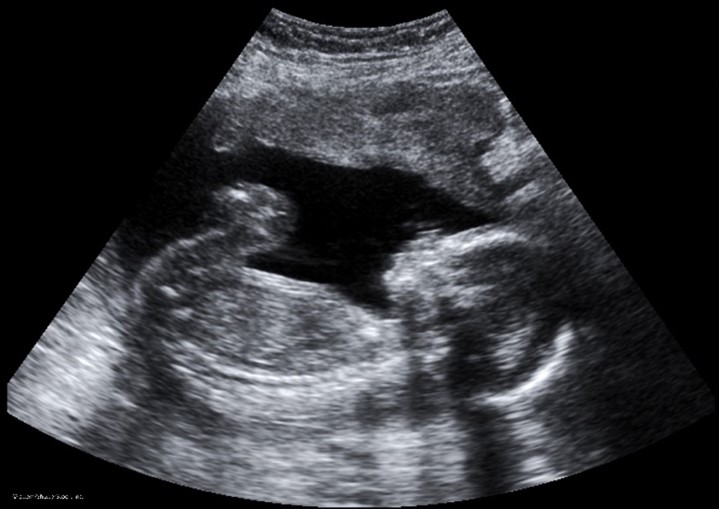

Ultrasound